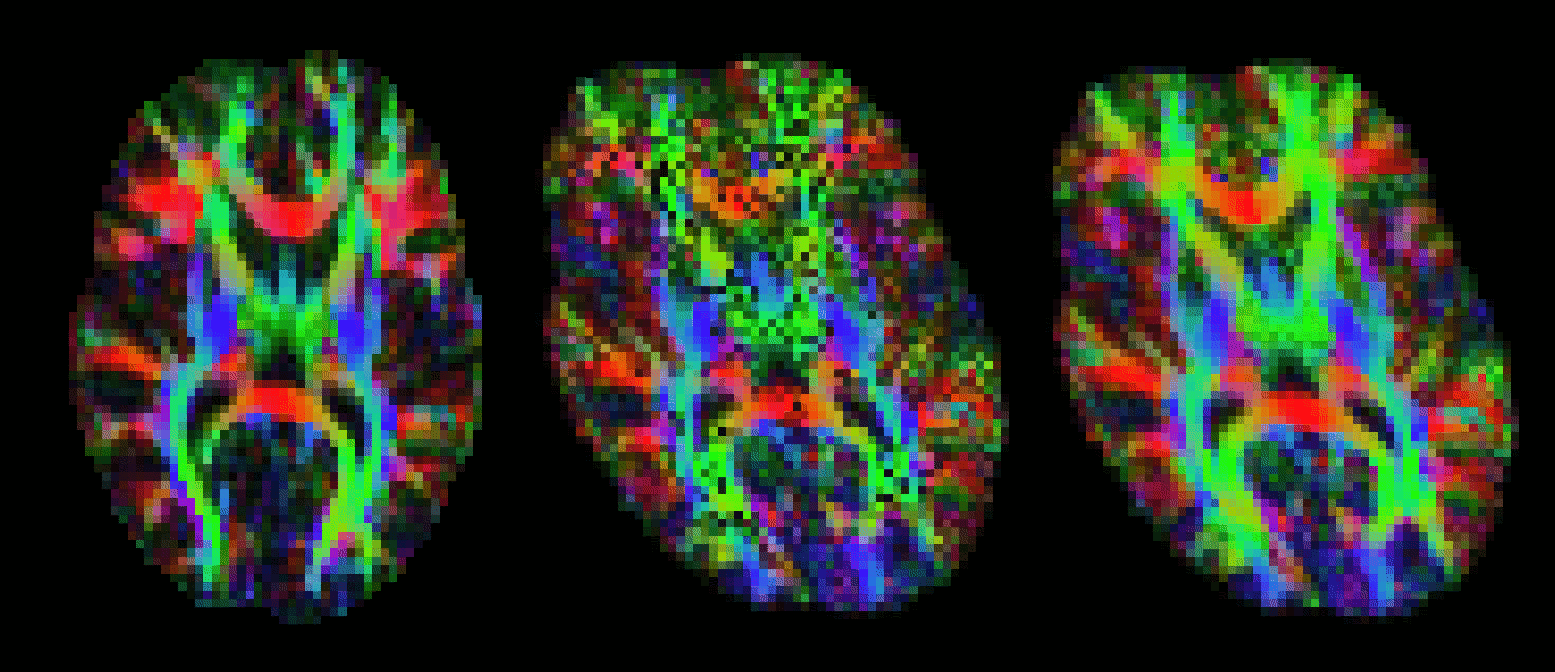

vecreg performs this operation for you. The image below shows the effect of applying vecreg (right) to the V1 image on the left, compared to simply applying voxelwise transformation (e.g. using applyxfm4D) to the vectors (centre).